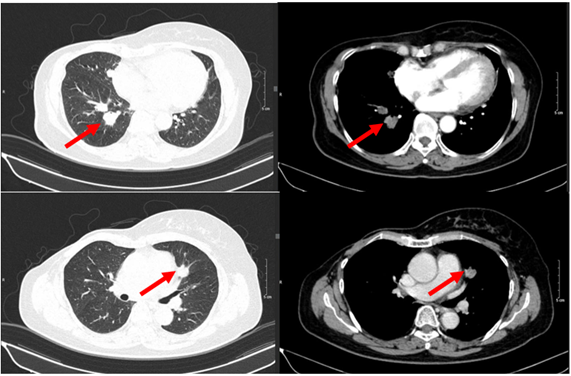

– Chụp cắt lớp vi tính ngực:

+ Thành ngực phải có nốt đặc kích thước khoảng 11x9mm – theo dõi tổn thương tái phát

+ Phổi phải: nhu mô thuỳ giữa và dưới có các khối – nốt đặc, lớn nhất 19x18mm

+ Phổi trái: nhu mô thuỳ trên và đáy phổi sát màng phổi có các khối nốt đặc, lớn nhất 16x17mm

Hình 1. Hình ảnh chụp CT ngực trước điều trị: Tổn thương tái phát thành ngực

Hình 2. Hình ảnh chụp CT ngực trước điều trị: Tổn thương phổi 2 bên